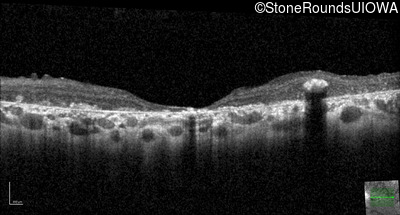

Optical Coherence Tomography - Left - 20/250 sc

Exemplar / OCT Stack